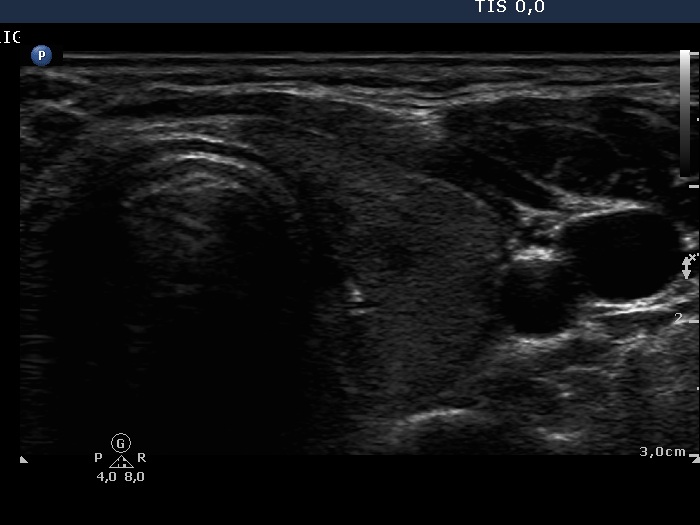

First examination (1st row of images)

Clinical data: A 29-year-old woman requested a second opinion. She was treated for Graves' disease for 2 months. The TSAb was initially 8.9 U/L, the FT4 was 54.2 pM/l. She get 30 mg methimazole therapy. Her complaints have already decreased.

Palpation: no abnormality.

Results of blood test: hyperthyroidism - TSH undetectable, FT4 29.2 pM/L, FT3 8.91 pM/L.

Ultrasonography: The thyroid was minimally enlarged and moderately hypoechogenic. The vascularization was a bit increased.

The dose of methimazole was reduced to daily 15 mg.